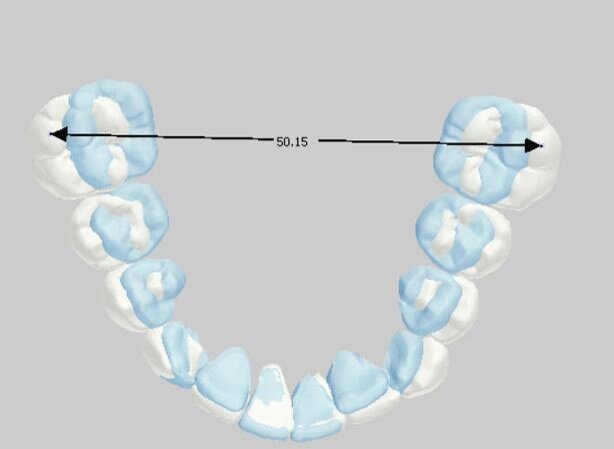

_Materiale e metodi Una paziente di sesso femminile di 11 anni, presenta all’esame clinico: dentizione permanente, palato di forma ogivale, discrepanza trasversale, affollamento e contrazione dell’arcata superiore, tipping vestibolare dei primi molari superiori, marcato affollamento dentale inferiore, tipping linguale degli elementi dentali postero-inferiori, proinclinazione vestibolare degli incisivi inferiori (Fig. 1). La paziente, inoltre, riferisce il menarca sei mesi prima dell’inizio della terapia. Per prima cosa è stato realizzato un setup digitale del risultato finale nell’arcata inferiore correggendo l’affollamento mediante espansione dei settori posteriori e minimizzando la proinclinazione degli incisivi. Utilizzando questo setup digitale come arcata guida, è risultata una discrepanza trasversale tra arcata inferiore e arcata superiore di circa 6 mm (Fig. 2).Richiesto l’esame CBCT, è stata valutata anche la morfologia della sutura palatina ed è risultata di tipo C secondo la classificazione di Angelieri et al11 (Fig. 3).

Fig. 2_Setup finale della correzione dell’arcata inferiore: nell’immagine è rappresentato in blu la posizione iniziale della dentatura, in bianco la posizione risultante dal setup. La lunghezza trasversale prevista a fine terapia sarà di 50 mm.